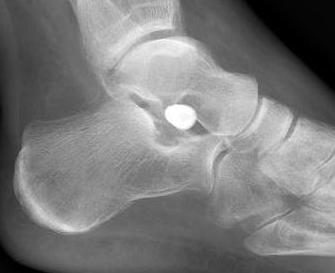

Subtalar arthroeresis

implantimplantimplant

Sinus tarsi implants limit excessive pronation

Endosinotarsal - implant in the sinus tarsi

ArthroArthro

Exosinotarsal - screw external to the sinus tarsi

Sabry et al JBJS Rev 2024

- systematic review of endo- v exosinotarsal implants for flexible flatfoot

- 6 studies and 800 feet

- increased pain and screw breakage in exosinotarsal

- increased implant dislocation in endosinotarsal